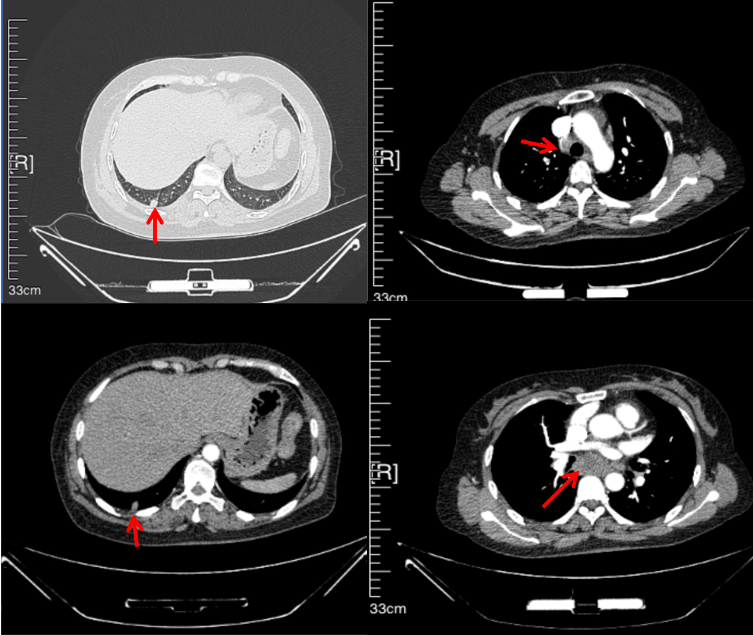

2016年1月复查CT提示支气管截断可见新发小结节,一线治疗采用培美曲塞+DDP方案化疗4周期(培美曲塞3.36,DDP 480mg)。化疗后复查胸部CT:右肺见不规则结节样影,最大层面大小约19mm*8mm,较前比较明显增大,疗效评估PD。2017.3-2017.4予单药多西他赛化疗3周期,疗效评估SD。2018年5月末复查CT提示结节较前增大,评效为PD,2018年6-10月予多西他赛+CBP化疗4周期,疗效评估SD。2022年5月患者出现活动后气短,复查胸部CT示右肺膨胀不良;右侧胸腔积液增多。胸腔积液包埋病理示符合肺腺癌细胞。行NGS基因检测:EML4:exon13-ALK:exon20融合。PD-L1(克隆号22C3)TPS<1%。

2018.07

2022.05

2022.08

2023.05